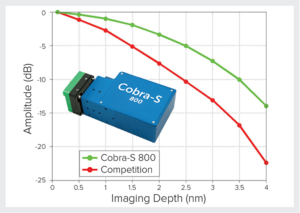

Wasatch Photonics公司生产的Cobra-S超高速OCT光谱仪在谱域光学相干层析(SD-OCT)中开创了一个新的时代。Cobra-S 800 OCT光谱仪是经过行业验证的高通量光谱仪设计、无热光机械和市场上最快相机的结合体。它在进行超高分辨率成像时不但拥有高于常规OCT光谱仪2-3倍的扫描速率,还拥有优于常规OCT光谱仪至少40%的滚降和更高的相机灵敏度。

▲上图显示与常规 OCT 光谱仪相比,Cobra-S 800的滚降至少优于竞争者40%,并且拥有更高的相机灵敏度

此外Cobra-S 800 OCT光谱仪在250kHz扫描速度和2.5mm成像深度时其滚降< 6dB,成为了扫频光学相干层析(SS-OCT)的主要挑战者。其扫描速度和滚降接近于扫频光学相干层析(SS-OCT),同时具有低成本和高分辨率的优势。